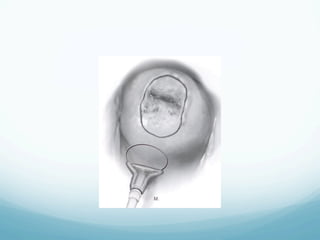

Cryosurgery

—  A thin layer of water-soluble lubricant is applied

—  The probe should cover the entire lesion, and a 4-5

mm ice ball around the probe is required for an

—  Repeat freeze thaw cycles will produce greater

tissue volume destruction than single freeze cycles

for the same amount of time provided

Cryosurgery —  A thinlayer of water-soluble lubricant is applied over the tip of the probe to allow more uniform and rapid freeze of the cervix —  The probe should cover the entire lesion, and a 4-5 mm ice ball around the probe is required for an adequate freeze —  Repeat freeze thaw cycles will produce greater tissue volume destruction than single freeze cycles for the same amount of time provided